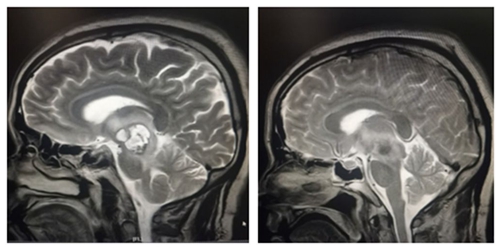

术前肿块影像                                                术后全切影像